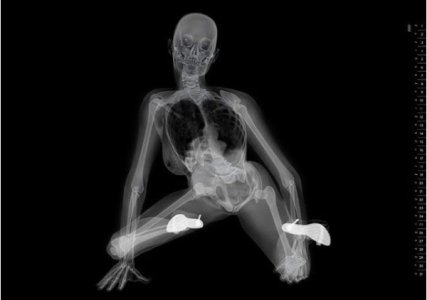

половой акт в разрезе, УЗИ, секс на рентгене

sex x-ray video

секс на томографе MRI

секс изнутри, половой акт в разрезе

как это снимал доктор Pek van Andel